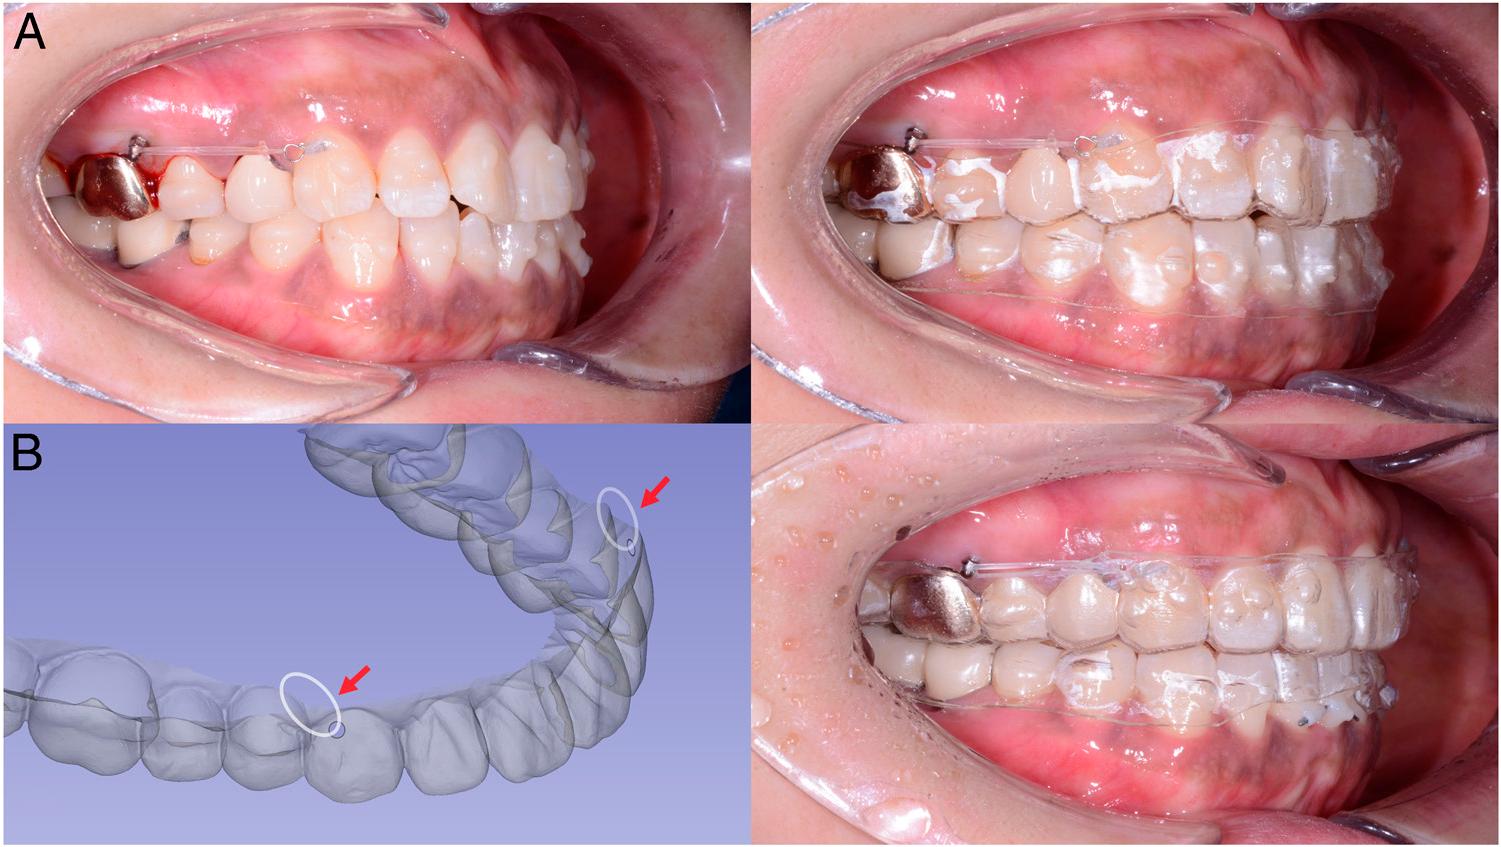

Figure 5.

Figure 6.